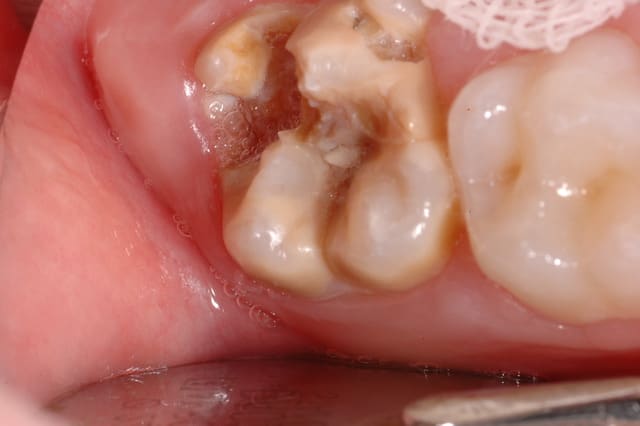

Le patient ci-dessous m'est adressé car ayant un "problème d'émail". Diagnostic ?

Biberon à la grenadine ??

J'aurais aussi pensé à "la carie du biberon"

Image odged8 - Eugenol

caries du biberon

les inc inf definitives st "encore" saines mais ça ne va pas durer :sois convaincant ds ta motivation:)